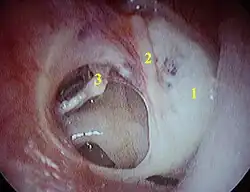

Geperforeerd trommelvlies (van linkeroor):

1 - Tympanosclerose, 2 - Hamer, 3 - bovenkant van stijgbeugel